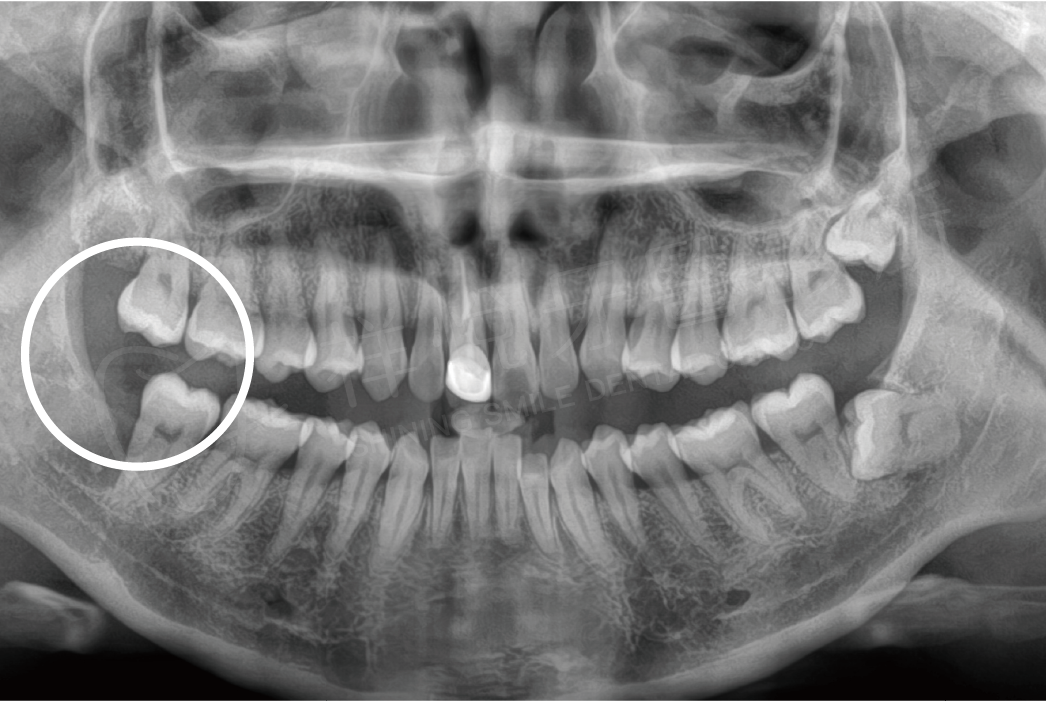

阻生齒拔除

拔牙前 拔牙後

拔牙前

拔牙後